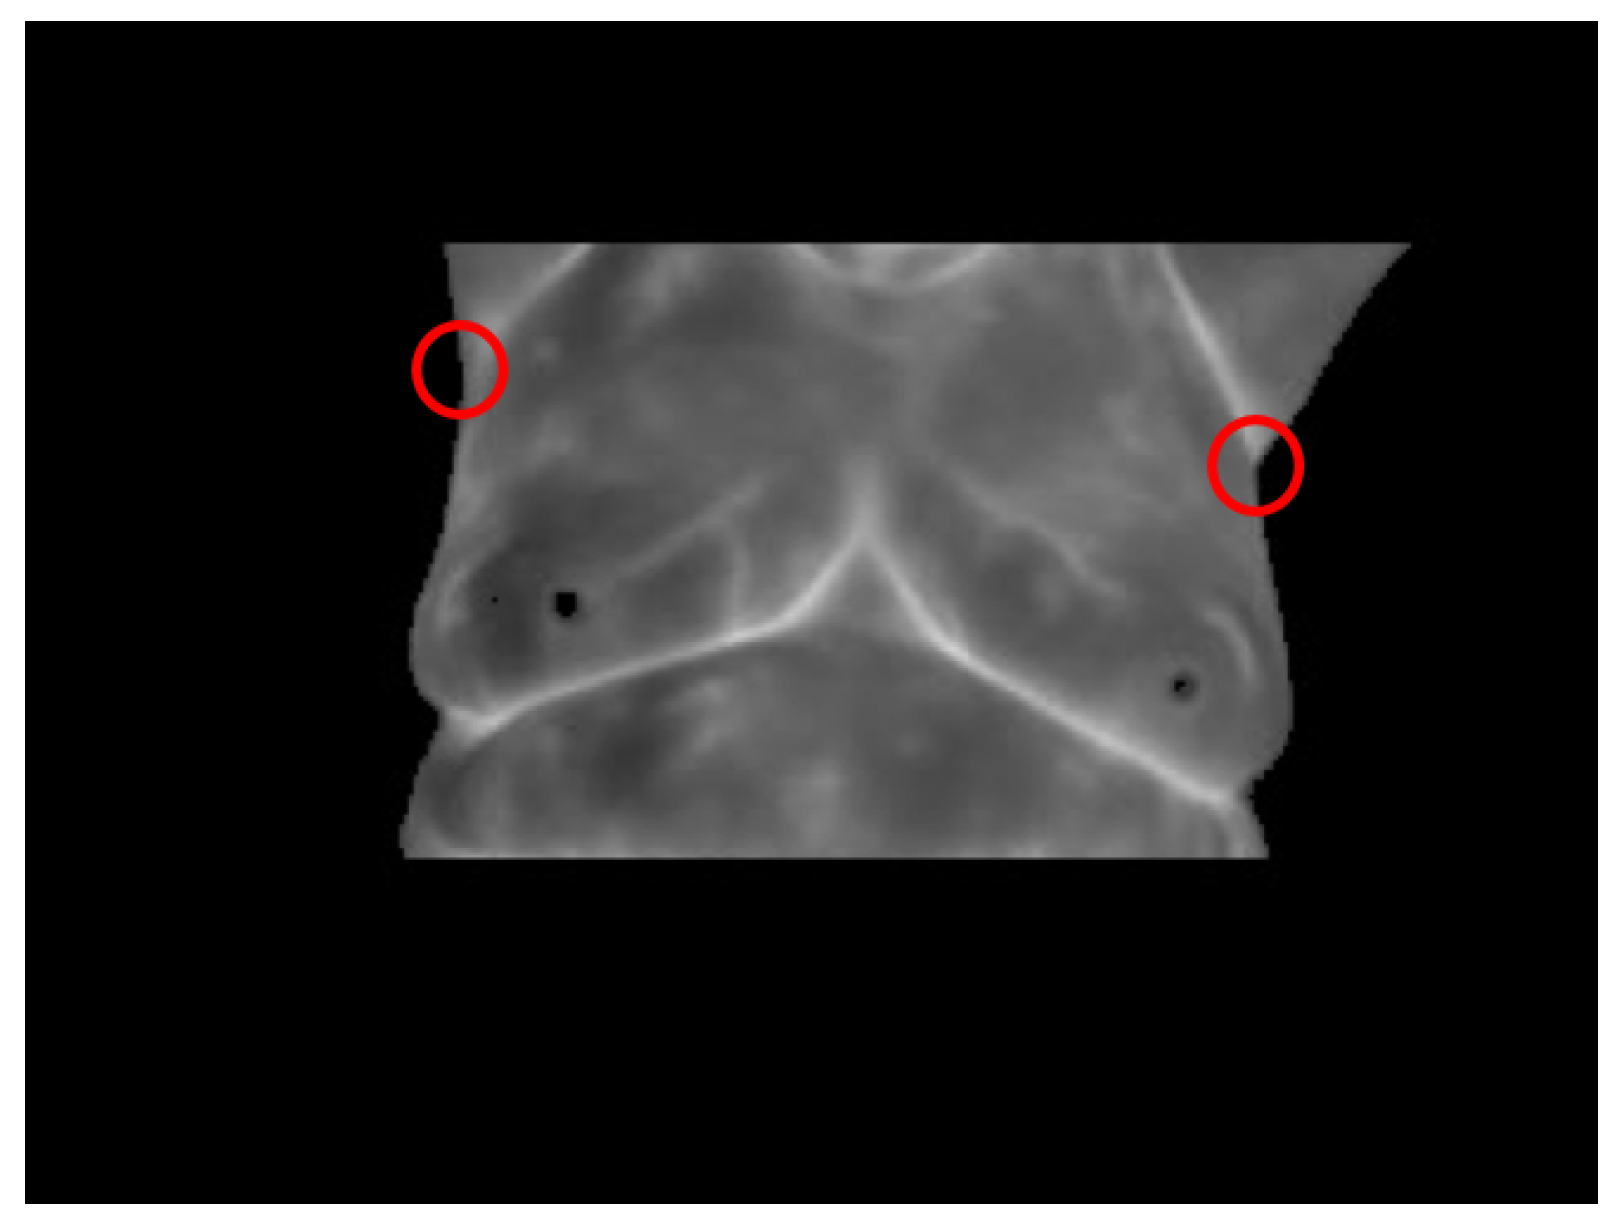

- Case 4, breast cancer:The last case can be seen in Figure 19. The acquired thermogram is shown in Figure 20a. The detection of the breast inferior limits can be seen in Figure 20b–d; meanwhile, the segmented right and left breast are depicted in Figure 20e,f. In the previous two cases, a more uniform temperature distribution was noticeable; in this case, however, multiple regions with high temperatures can be seen in Figure 20a in lighter shades of gray getting close to white. Although a qualitative analysis is not the objective of this paper, such information can be used to infer the existence of a problem that must be analyzed.Posterior to the breast segmentation, the evaluation process delivers the results shown in Table 7. As can be seen, the average temperature difference is 1.92 °C, which is slightly superior to that presented in Case 3. The maximum value and standard deviation present the highest difference of the four cases analyzed, reaching a value of 8.53 °C for the first one and 2.46 °C for the second one.With the numeric result establishing a difference of temperatures between right and left breast higher than 1 °C, the additional step, which implies spotting the location of the hottest region, is performed. Watershed segmentation applied to the right breast, which results in being the one with the highest temperature average, is shown in Figure 21, with the region with the highest temperature denoted in gray and indicated within a red circle; such a region is located in the lower zone of the breast, and the expert is recommended to be aware of it.